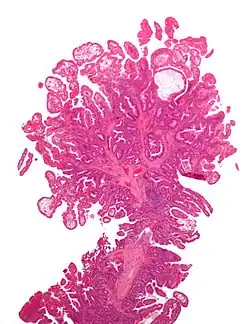

| Tubulovillous adenoma | 20% to 25%[15] | 25–75% villous[14] |

The common adenomas of the colon (colorectal adenoma) are the tubular, tubulovillous, villous, and sessile serrated (SSA).[18] A large majority (65–80%) are of the benign tubular type with 10–25% being tubulovillous, and villous being the most rare at 5–10%.[9]

- Tubulovillous adenoma: 20% risk of cancer